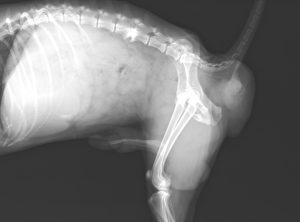

レントゲン画像では通常とは異なる位置に糞便の陰影が見られます。